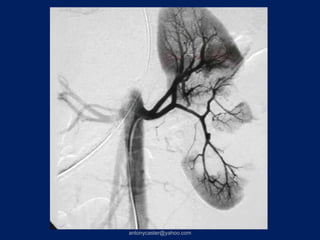

• Técnicas mínimamente invasivas:

- Angioembolización

- Drenaje de abscesos hepáticos o

bilomas guiado por TAC o US.

- Laparoscopía para peritonitis biliar

- CPRE para fugas biliares.

• Cirugía

Tratamiento de complicaciones •Técnicas mínimamente invasivas: - Angioembolización - Drenaje de abscesos hepáticos o bilomas guiado por TAC o US. - Laparoscopía para peritonitis biliar - CPRE para fugas biliares. • Cirugía